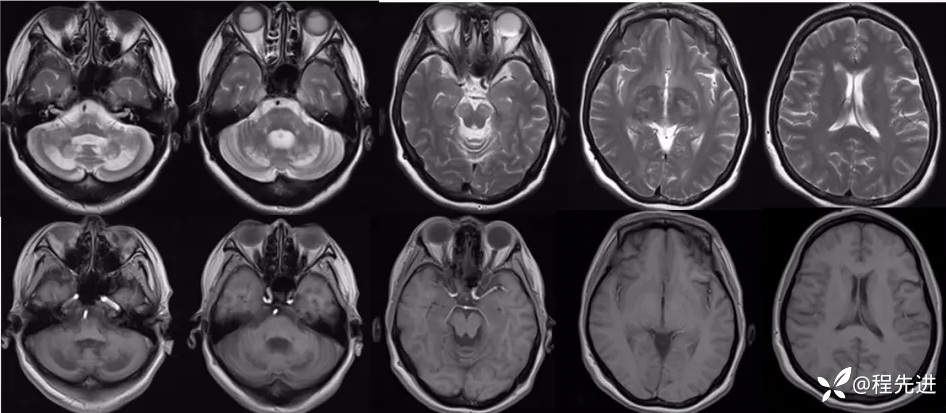

T2、T1: